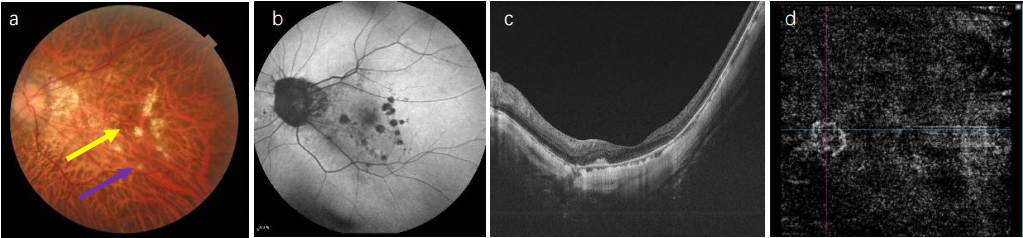

Typically, myopic CNV presents as a small, flat, grayish subretinal membrane, located between the neurosensory retina and the retinal pigment epithelium (RPE), often near the fovea, with or without associated hemorrhage.[12-13] On optical coherence tomography (OCT), these lesions appear as highly reflective signals with blurred upper boundaries of the RPE cells (Fig.1, typical of type 2 macular neovascularization) and are usually associated with minimal subretinal fluid.[14]The determination of activity on OCT mainly relies on four signs:[15] 1) intraretinal or subretinal fluid, 2) subretinal hyperreflective material, 3) disruption of the external limiting membrane, and 4) blurred lesion boundaries. Optical coherence tomography angiography (OCTA) is a valuable tool for detecting myopic CNV, showing a vascular network pattern in the outer retina and choriocapillaris slab, with high sensitivity (90.48%) and specificity (93.75%).[16] On OCTA, the assessment of activity is based on four indicators:[17] 1) a jellyfish-like or sea fan-shaped appearance of myopic macular neovascularization lesions, 2) numerous tiny capillary branches, 3) presence of vascular anastomoses or loops, and 4) a dark halo surrounding the lesion. The combined use of these methods can improve the sensitivity and specificity of activity assessment. However, fluorescein fundus angiography (FFA) remains the gold standard for diagnosis, showing early-phase well-defined hyperfluorescence of the lesion with late-phase fluorescent leakage. Indocyanine green angiography (ICGA) shows that ICG is minimally absorbed by the RPE and blood, allowing better differentiation of CNV from other pathologies, especially when hemorrhage is present.

Figure 1 Multimodal imaging of macular hemorrhage in pathological myopia-associated choroidal neovascularization (myopic CNV).